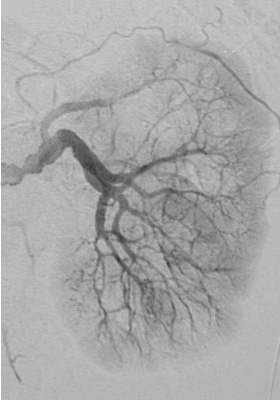

Another study is performed, as shown below:

Following administration of the ACE inhibitor, there is marked asymmetry in renal function, with normal uptake and excretion by the right kidney but little or no excretion on the left. This test is a good screening tool for renovascular hypertension.